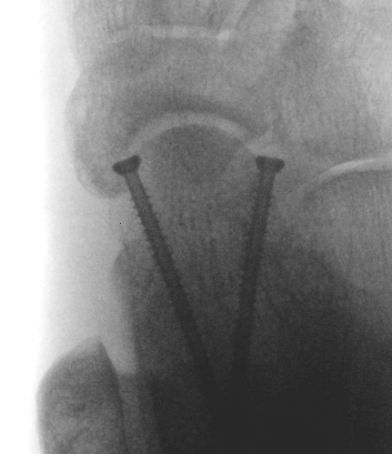

Cannulated screws

Xrays

| AP | Lateral | Canale View |

|---|---|---|

| Entry point of the screws |

Evaluate neck reduction

|

Evaluates the neck reduction |

Lateral off articular surface Medial through articular cartilage |

Depth of screws |

Beam angled 75o to foot Foot 15o pronated |

1. Retrograde (anterior to posterior) into posterior talus body

A. Lateral screw

- insert proximal to articular surface of head on lateral side

- bone is very curved here

- can lag screw as usually no comminution

B. Medial side

- insert through articular surface

- countersunk screws through articular surface

- avoid lag screw techniques medially as may compress comminution into varus

AP, Canale and Lateral xray

Retrograde screws